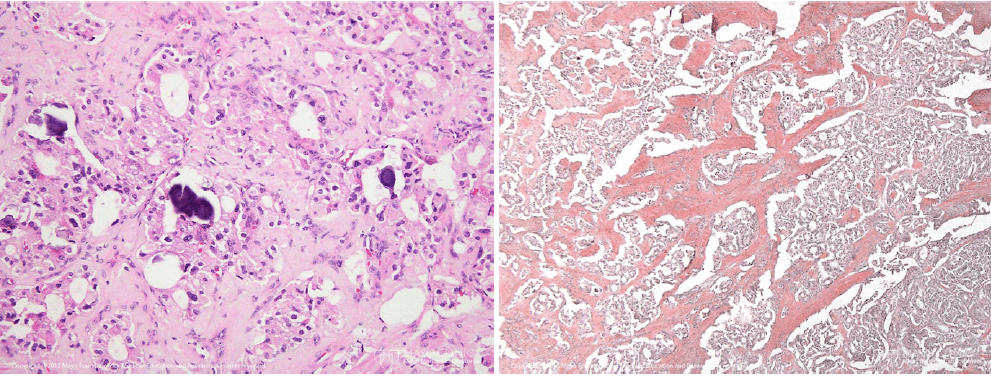

Aproximadamente 2/3 dos somatostatinomas do duodeno apresentam corpos de psamoma característicos dentro de espaços pseudoglandulares, característica não verificada em somatostatinomas pancreáticos. Esta entidade é um subtipo específico de um tumor neuroendócrino bem diferenciado, com núcleos monomórficos, cromatina pontilhada e citoplasma eosinófilo finamente granulado, bem como estrutura aninhada, trabecular ou insular. Neste caso, o amilóide foi subclassificado como somatostatina por cromatografia líquida acoplada à espectrometria de massas. A maioria dos somatostatinomas do duodeno está localizada na região ampular ou periampular, mais frequentemente com apresentação clínica de dor abdominal e, às vezes, com outros sintomas obstrutivos das vias biliares. Normalmente, a síndrome de somatostatinoma, que inclui diabetes mellitus, diarreia e/ou esteatorreia, colelitíase, hipocloridria, perda de peso e anemia, não está associada ao somatostatinoma do duodeno. A síndrome de somatostatinoma pode manifestar-se numa minoria de pacientes com somatostatinoma pancreático. Os somatostatinomas do duodeno estão associados a diversas síndromes genéticas, principalmente a NF1; tanto o somatostatinoma do duodeno como o pancreático apresentam associações com MEN1 e VHL. Uma síndrome que compreende policitemia, paragangliomas múltiplos e somatostatinoma do duodeno também foi identificada recentemente.

Esta é a neoplasia invasiva mais comum no duodeno, e o somatostatinoma é capaz de imitá-la; na verdade, foi usado o termo “tumor neuroendócrino psamomatoso glandular do duodeno”. Apesar das formações ganglionares, este caso não tem as características estruturais e citológicas de adenocarcinoma, como pleomorfismo celular, atipia, mitoses e produção de mucina.